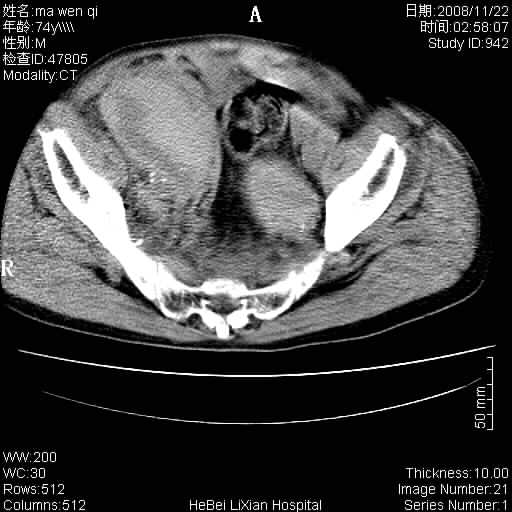

患者男 74岁.突然昏迷,休克6小时.血压70/30,头颅ct未见异常,既往体健.

补充病史,保留导尿10小时,尿袋内只有少许尿液,患者于住院后15小时后去世.

腹主动脉、双侧髂动脉夹层动脉瘤破裂出血进入腹腔。

考虑双侧髂a瘤,伴破裂出血

腹主动脉、双侧髂动脉夹层或动脉瘤破裂出血进入腹腔

1)考虑双侧髂动脉瘤并右侧动脉瘤破裂出血,右侧腹膜后及腹腔积血。2)双侧腹股沟疝。

支持(1)双侧髂动脉瘤并右侧动脉瘤破裂出血,右侧腹膜后及腹腔积血。(2)双侧腹股沟疝。

1)考虑,腹主动脉、双侧髂动脉夹层动脉瘤破裂伴右侧腹膜后及腹腔积血。2)双侧腹股沟疝。

1)考虑胸、腹主动脉、双侧髂动脉瘤并右侧动脉瘤破裂出血,右侧腹膜后及腹腔积血。2)双侧腹股沟疝。